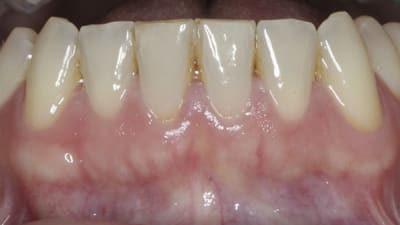

Research Orthodontics The Impact of Orthodontic Retainers on Gingival Recession: A Best-Evidence Review By John Paul Mussleman, Jr., Nada M. Souccar, DDS, Nicolaas C. Geurs, DDS, Ramzi V. Abou-Arraj, DDS, Rawan Oueis, DDS March 01, 2022 17 min read